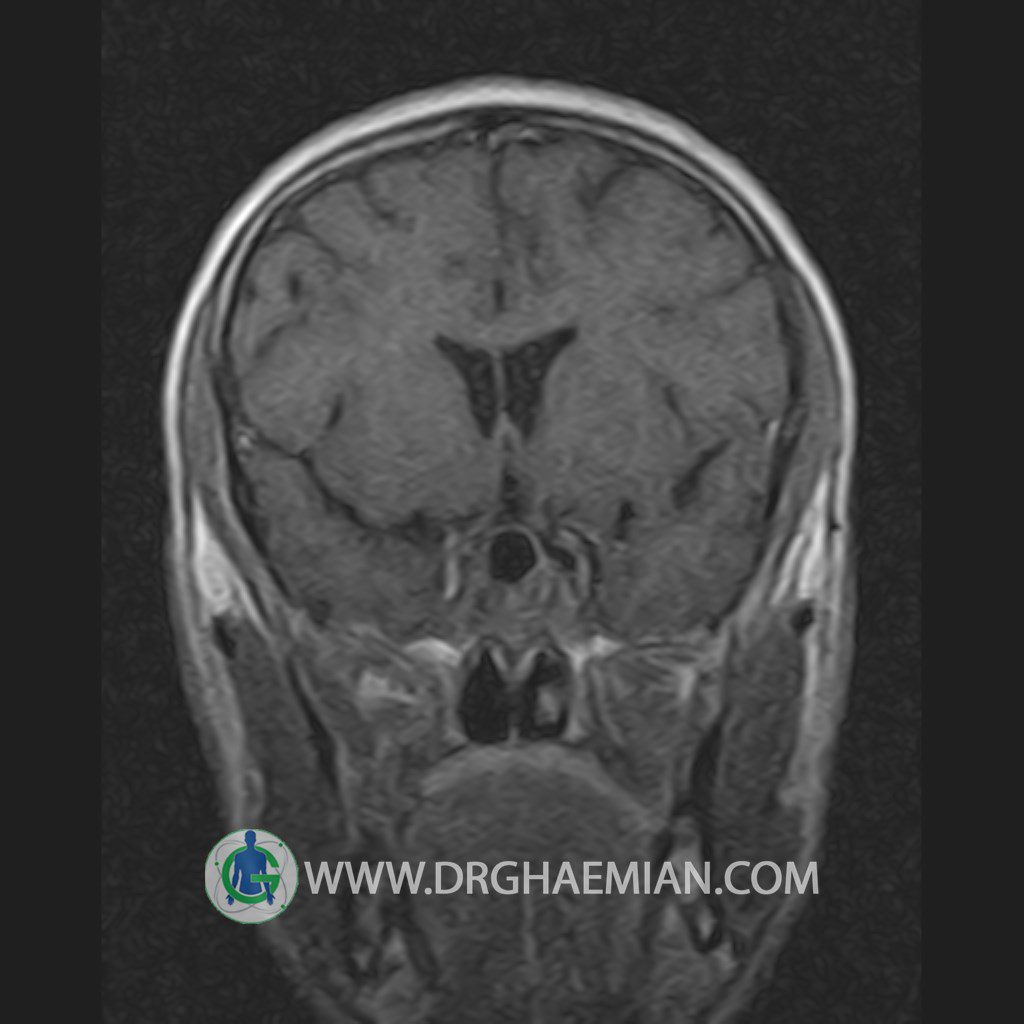

پزشکان اغلب از تصویربرداری ام آر آی برای تشخیص و درمان عارضه های پزشکی که فقط با استفاده از اشعه ایکس یا میدان مغناطیسی و امواج رادیویی قابل مشاهده است، استفاده می کنند. دستگاه ام آر آی تصاویر دقیق از ساختار های داخلی بدن ایجاد می کند. در این کیس یک میکروآدنوم در هیپوفیز بیمار مشاهده می شود.

HYPOPHYSIS MRI

(with and without contrast)

Technique: Axial , coronal T1 , Axial , coronal , sagittal T2 , Axial, coronal T1 post Gd & 64 dynamic thin coronal slices.

The infundibulum is centered and of normal size .

The optic chiasm and suprasellar spaces appear normal .

The cavernous sinus and imaged portions of the internal carotid artery and carotid siphon are unremarkable .

Evaluable portions of the neurocranium show no abnormalities .

The sphenoid sinus is clear and pneumatized .

Imaging of the hypothalamus after contrast medium administration was normal.

– Small hypoenhancing mass lesion ( 3 x 4 mm ) in posterior of pituitary stalk suggestive for micro adenoma

– Mucosal thickening in ethmoid & maxillary sinuses

is seen